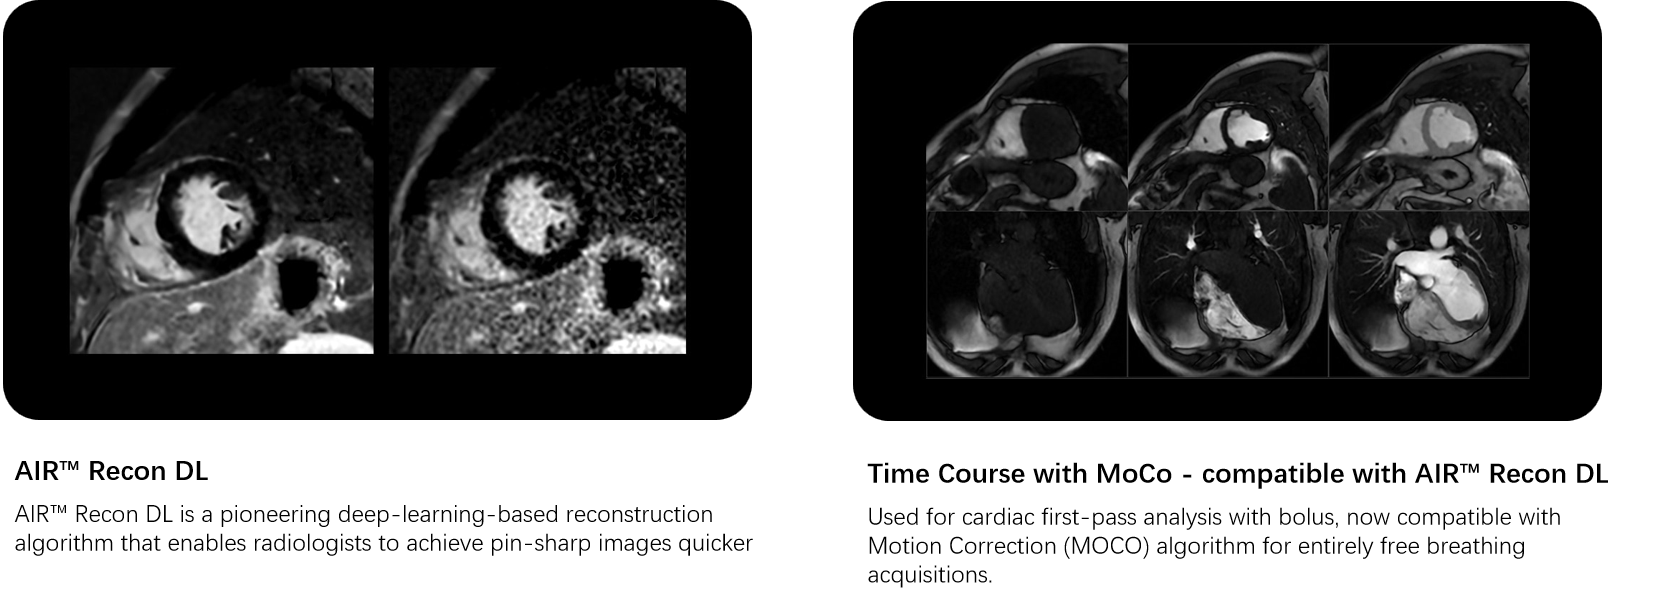

Cardiovascular MRI imaging applications

A COMPLETE CARDIAC PACKAGE

unBEATable SIGNA™ Cardiac MR Cardiac MR has been too slow, complex and inconsistent for too long1. Now with cardiac MR for SIGNA™, that’s all in the past. Experience accelerated diagnostics and crystal-clear imaging, powered by deep learning. From AI-boosted precision to lightning-fast scans, explore the seamless connection between innovation and patient-centric care..